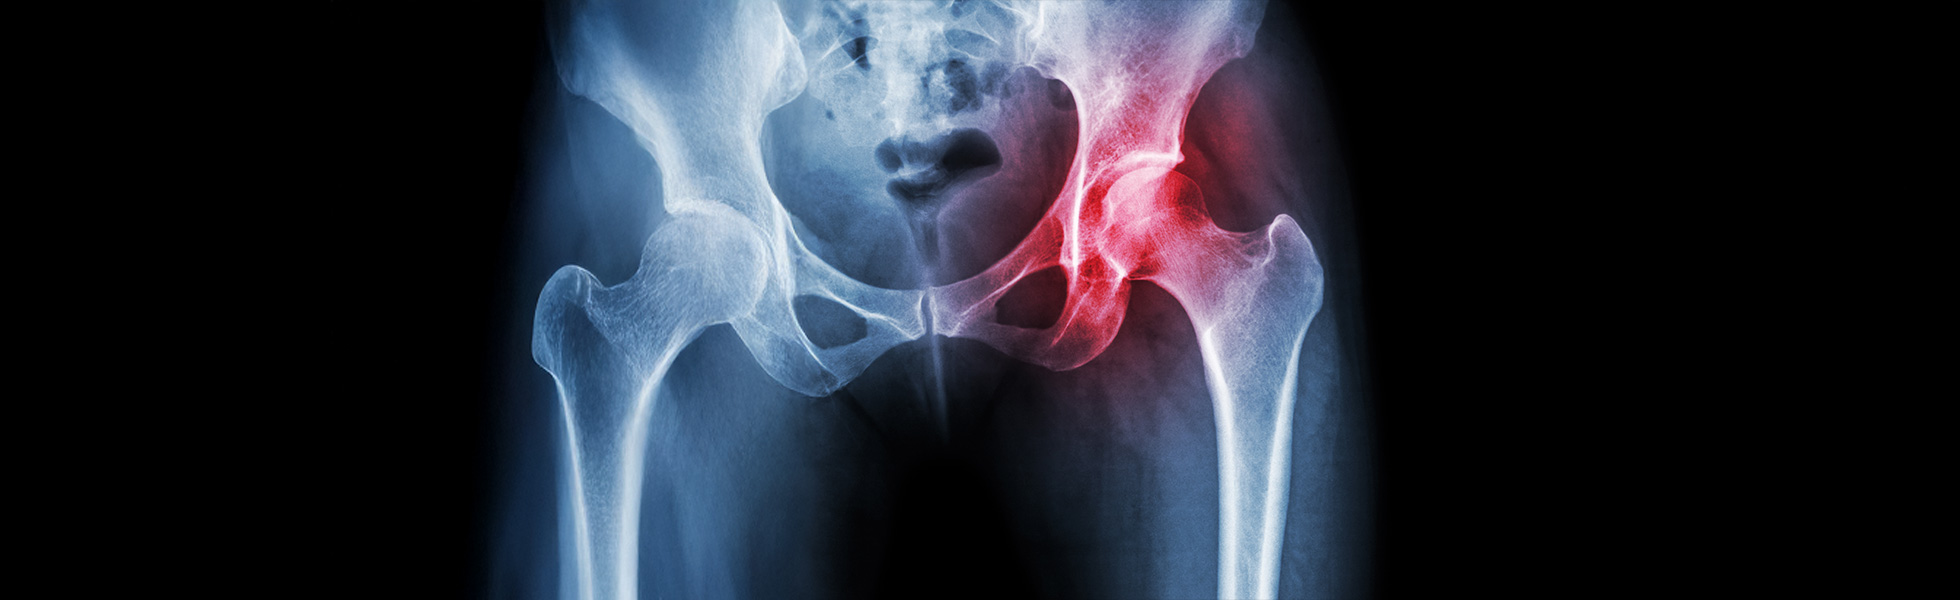

Anterior hip replacement is a minimally invasive surgical approach that accesses the hip joint from the front, significantly reducing muscle disruption and enhancing early recovery.

Anterior hip replacement involves replacing the damaged hip joint through an anterior (front) incision, minimising muscle trauma and enhancing postoperative outcomes.

Posterior hip replacement involves accessing the hip joint from the side or back, a traditionally effective method suitable for a variety of patient conditions.

The posterior approach accesses the hip joint through an incision from the side or back, a traditional and proven, reliable method for diverse surgical requirements.

Ideal candidates for anterior or posterior hip replacement experience significant hip pain, limited mobility, or dysfunction due to conditions such as osteoarthritis, rheumatoid arthritis, or other degenerative joint diseases that haven’t adequately responded to non-surgical treatments.